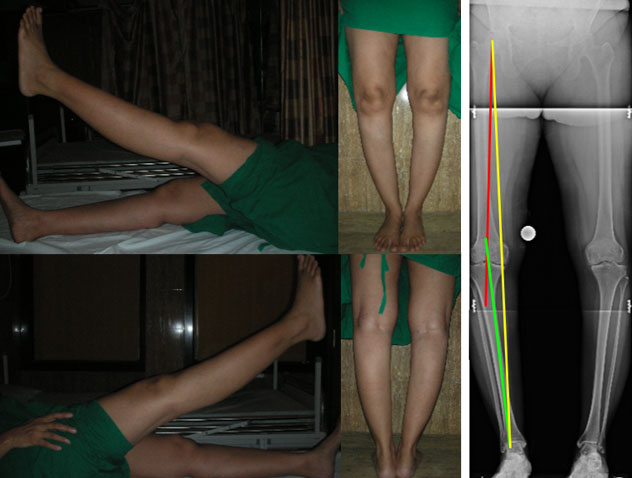

| Pre surgery |

| The clinical pics and full length x-ray before surgery show a significant varus deformity in both the tibiae. The right side was operated first as the right side was more painful. The yellow line on the x-ray shows the load bearing axis, which is passing through the inner side of the knee. The red and the green lines show the varus angulation (bowing of the leg). |